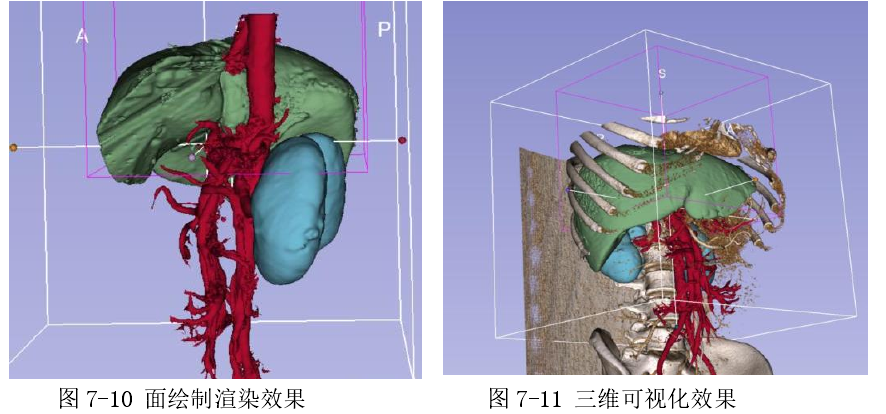

6.2.6 面绘制渲染效果

如图(图 7-6)基于经过分割算法分割出来的器官组织区域(案例中使用了肝脏肾脏和部分主动脉分割效果),使用面绘制移动立方体算法进行面绘制效果如下: